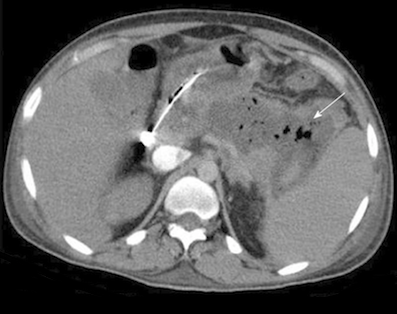

Elles sont suspectées devant un malade dont l’état clinique s’aggrave (apparition de nouvelles défaillances viscérales, augmentation de la température centrale), dont les marqueurs biologiques s’altèrent (élévation de la CRP, de la polynucléose neutrophile). La présence (rare) de bulles d’air dans les coulées de nécrose est très évocatrice de surinfection à germes anaérobies.

Figure n°1 : (flèche) : bulle d'air témoignant d'une infection

d'une coulée de nécrose